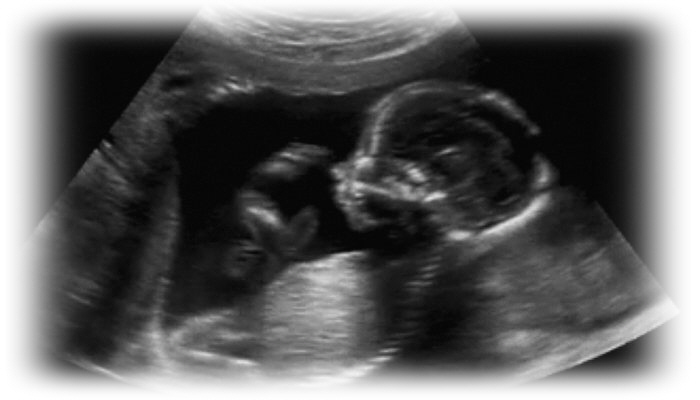

هل فترة حملك لم تتعدى بعد الـ 37 أسبوعا؟